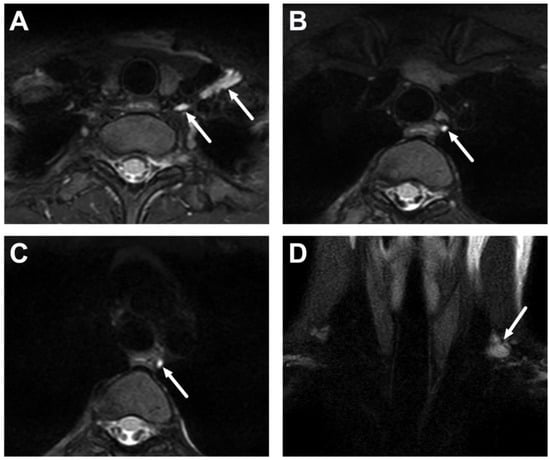

6.1. Mediastinitis